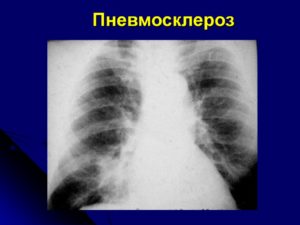

Пневмофиброз

Рентген грудной клетки

Рентгенография является одним из главных методов, помогающим определить наличие различных заболеваний легких. При пневмофиброзе органы дыхания сильно видоизменяются – усиливается и деформируется легочный рисунок, увеличиваются сосудистые тени. Легочные тени со рваными краями, расположенные хаотично, говорят о последних стадиях патологии.